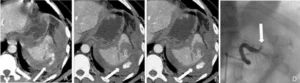

Figura A e B: immagine TC che documenta la sede della lesione arteriosa (freccia bianca). Figura C: la freccia bianca indica la sede dello stravaso extra-luminale di mezzo di contrasto, sede della emorragia. Figura D: chiusura della arteria che stava sanguinando (freccia bianca) e cessazione della emorragia.